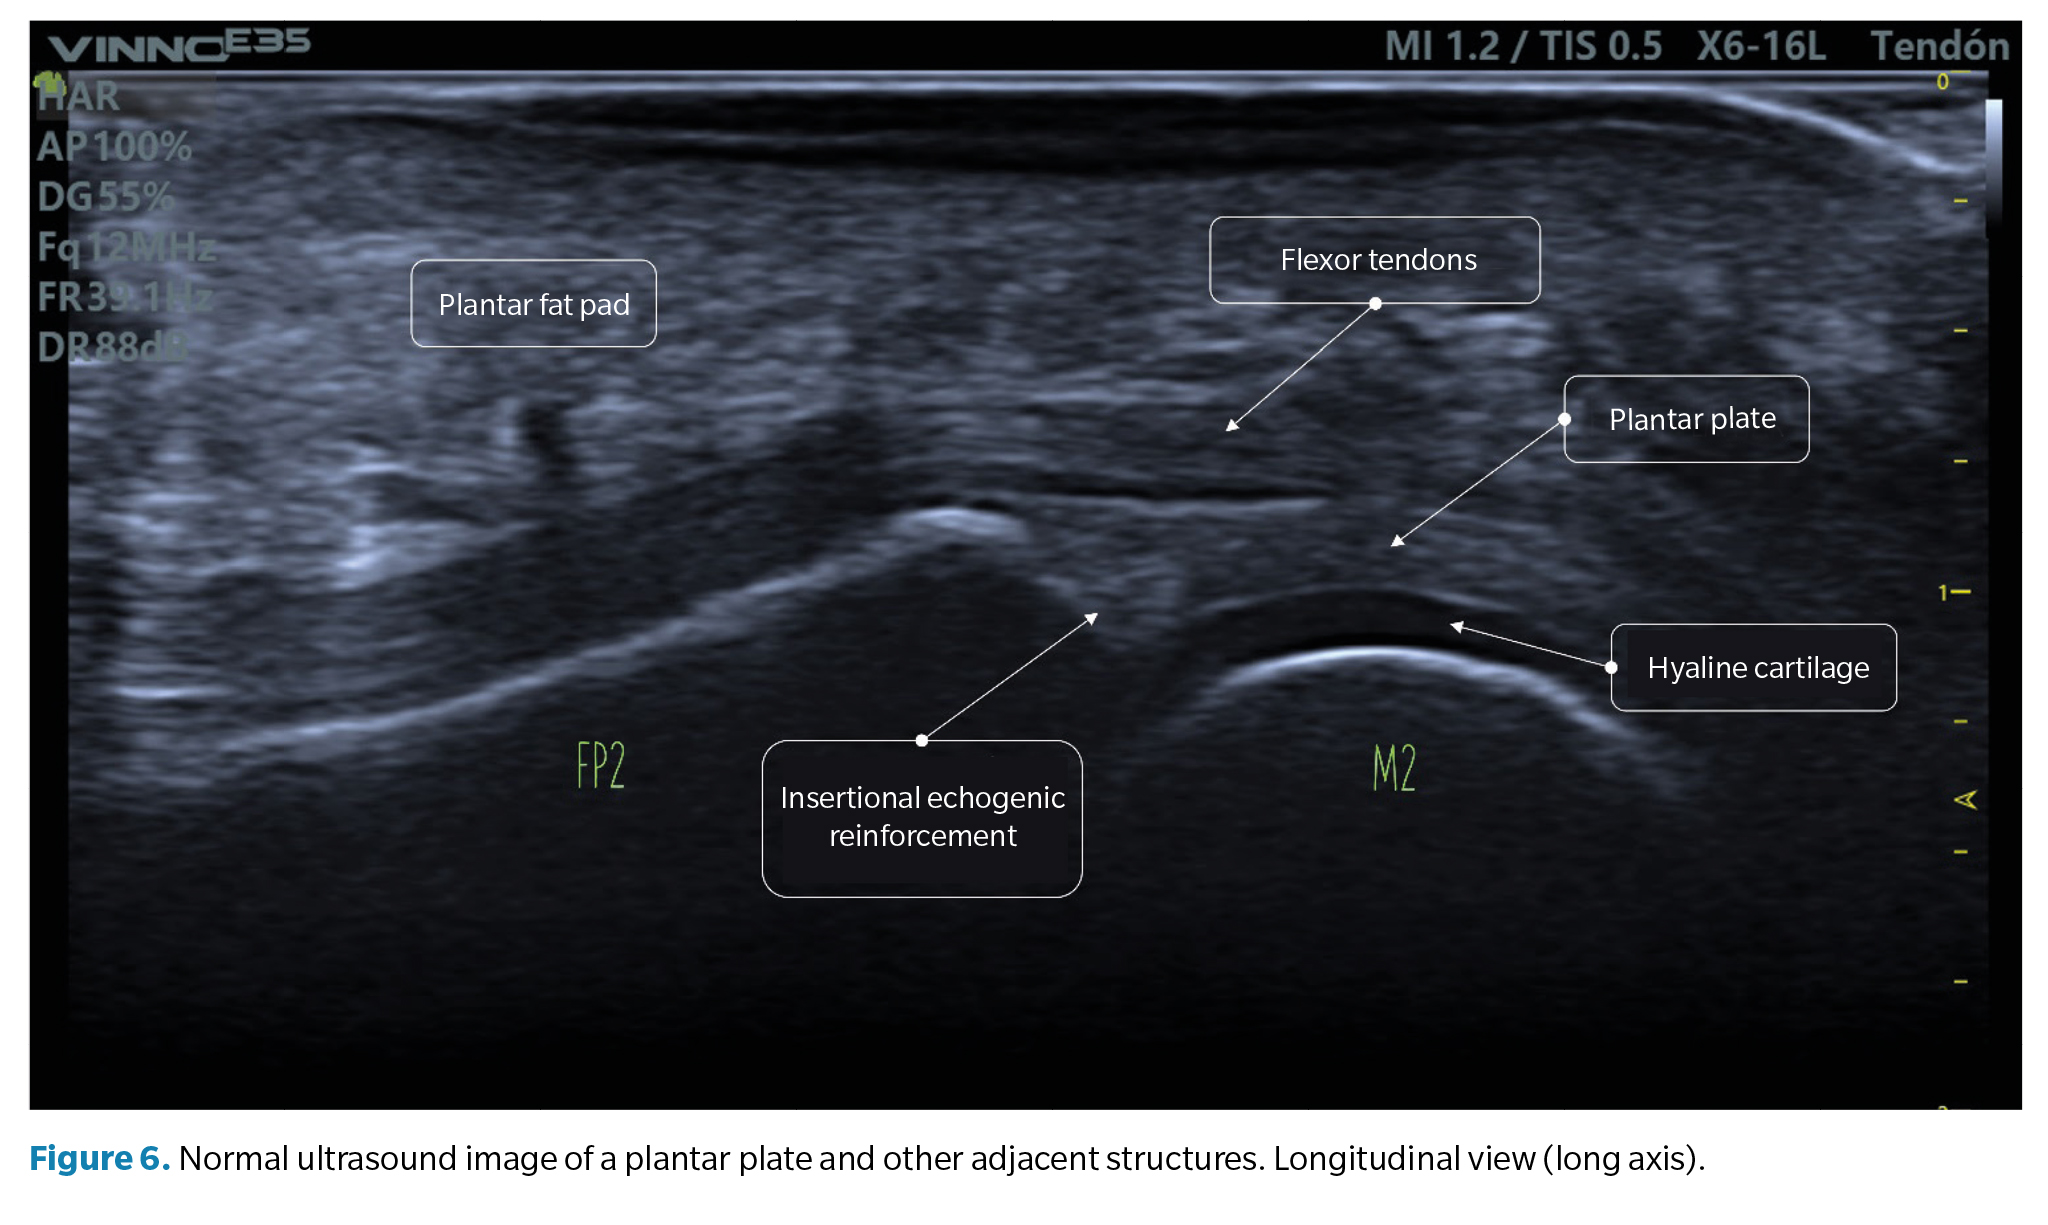

• Longitudinal view (long axis): the normal plantar plate appears on ultrasound as a slightly echogenic curvilinear structure with a homogeneous granular echotexture. This texture allows differentiation, not always well-defined, from the underlying flexor tendons with a fibrillar texture. The articular surface of the plate is precisely defined, bordering the hypoechoic hyaline cartilage of the metatarsal head (Figure 6).

At the junction with the proximal phalanx, which is well-defined, the bone contour is usually smooth, and a more echogenic triangular area may appear in the plate, described as a normal ultrasound finding and possibly representing a higher proportion of collagen fibers. The proximal junction with the metatarsal neck, however, has poor definition on the ultrasound image (Figure 6).